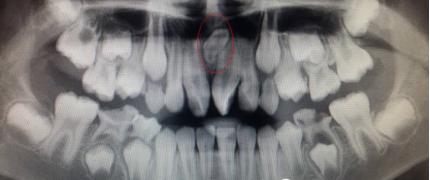

儿童口腔科的医生经过专科查体并配合X线检查,发现是孩子的两颗新长门牙之间有一颗多生牙在作怪,这让李奶奶更紧张了。

临床上发现或有多生牙时,需要拍摄X线片来明确诊断,如牙齿根尖片、全口曲面断层片或CBCT等,确定多生牙的数目和位置。为了减少多生牙对恒牙和恒牙列的影响,应尽早发现,及时处理。已经萌出的多生牙应及时拔除,以有利于邻近恒牙的顺利萌出并减少恒牙的错位。若萌出的多生牙形态与正常牙相似或牙根有足够的长度,而相邻的正常牙齿有牙根吸收、牙根弯曲等问题,可以综合考虑全牙列的情况后拔除相对较差的正常牙而保留多生牙。对于埋伏的多生牙,如果影响恒牙的发育、萌出及排列,在不损伤恒牙胚的情况下应尽早拔除,若不影响恒牙胚发育和萌出,则可等到恒牙牙根发育完成后再拔除。埋伏的多生牙拔除术后还要注意定期复查。